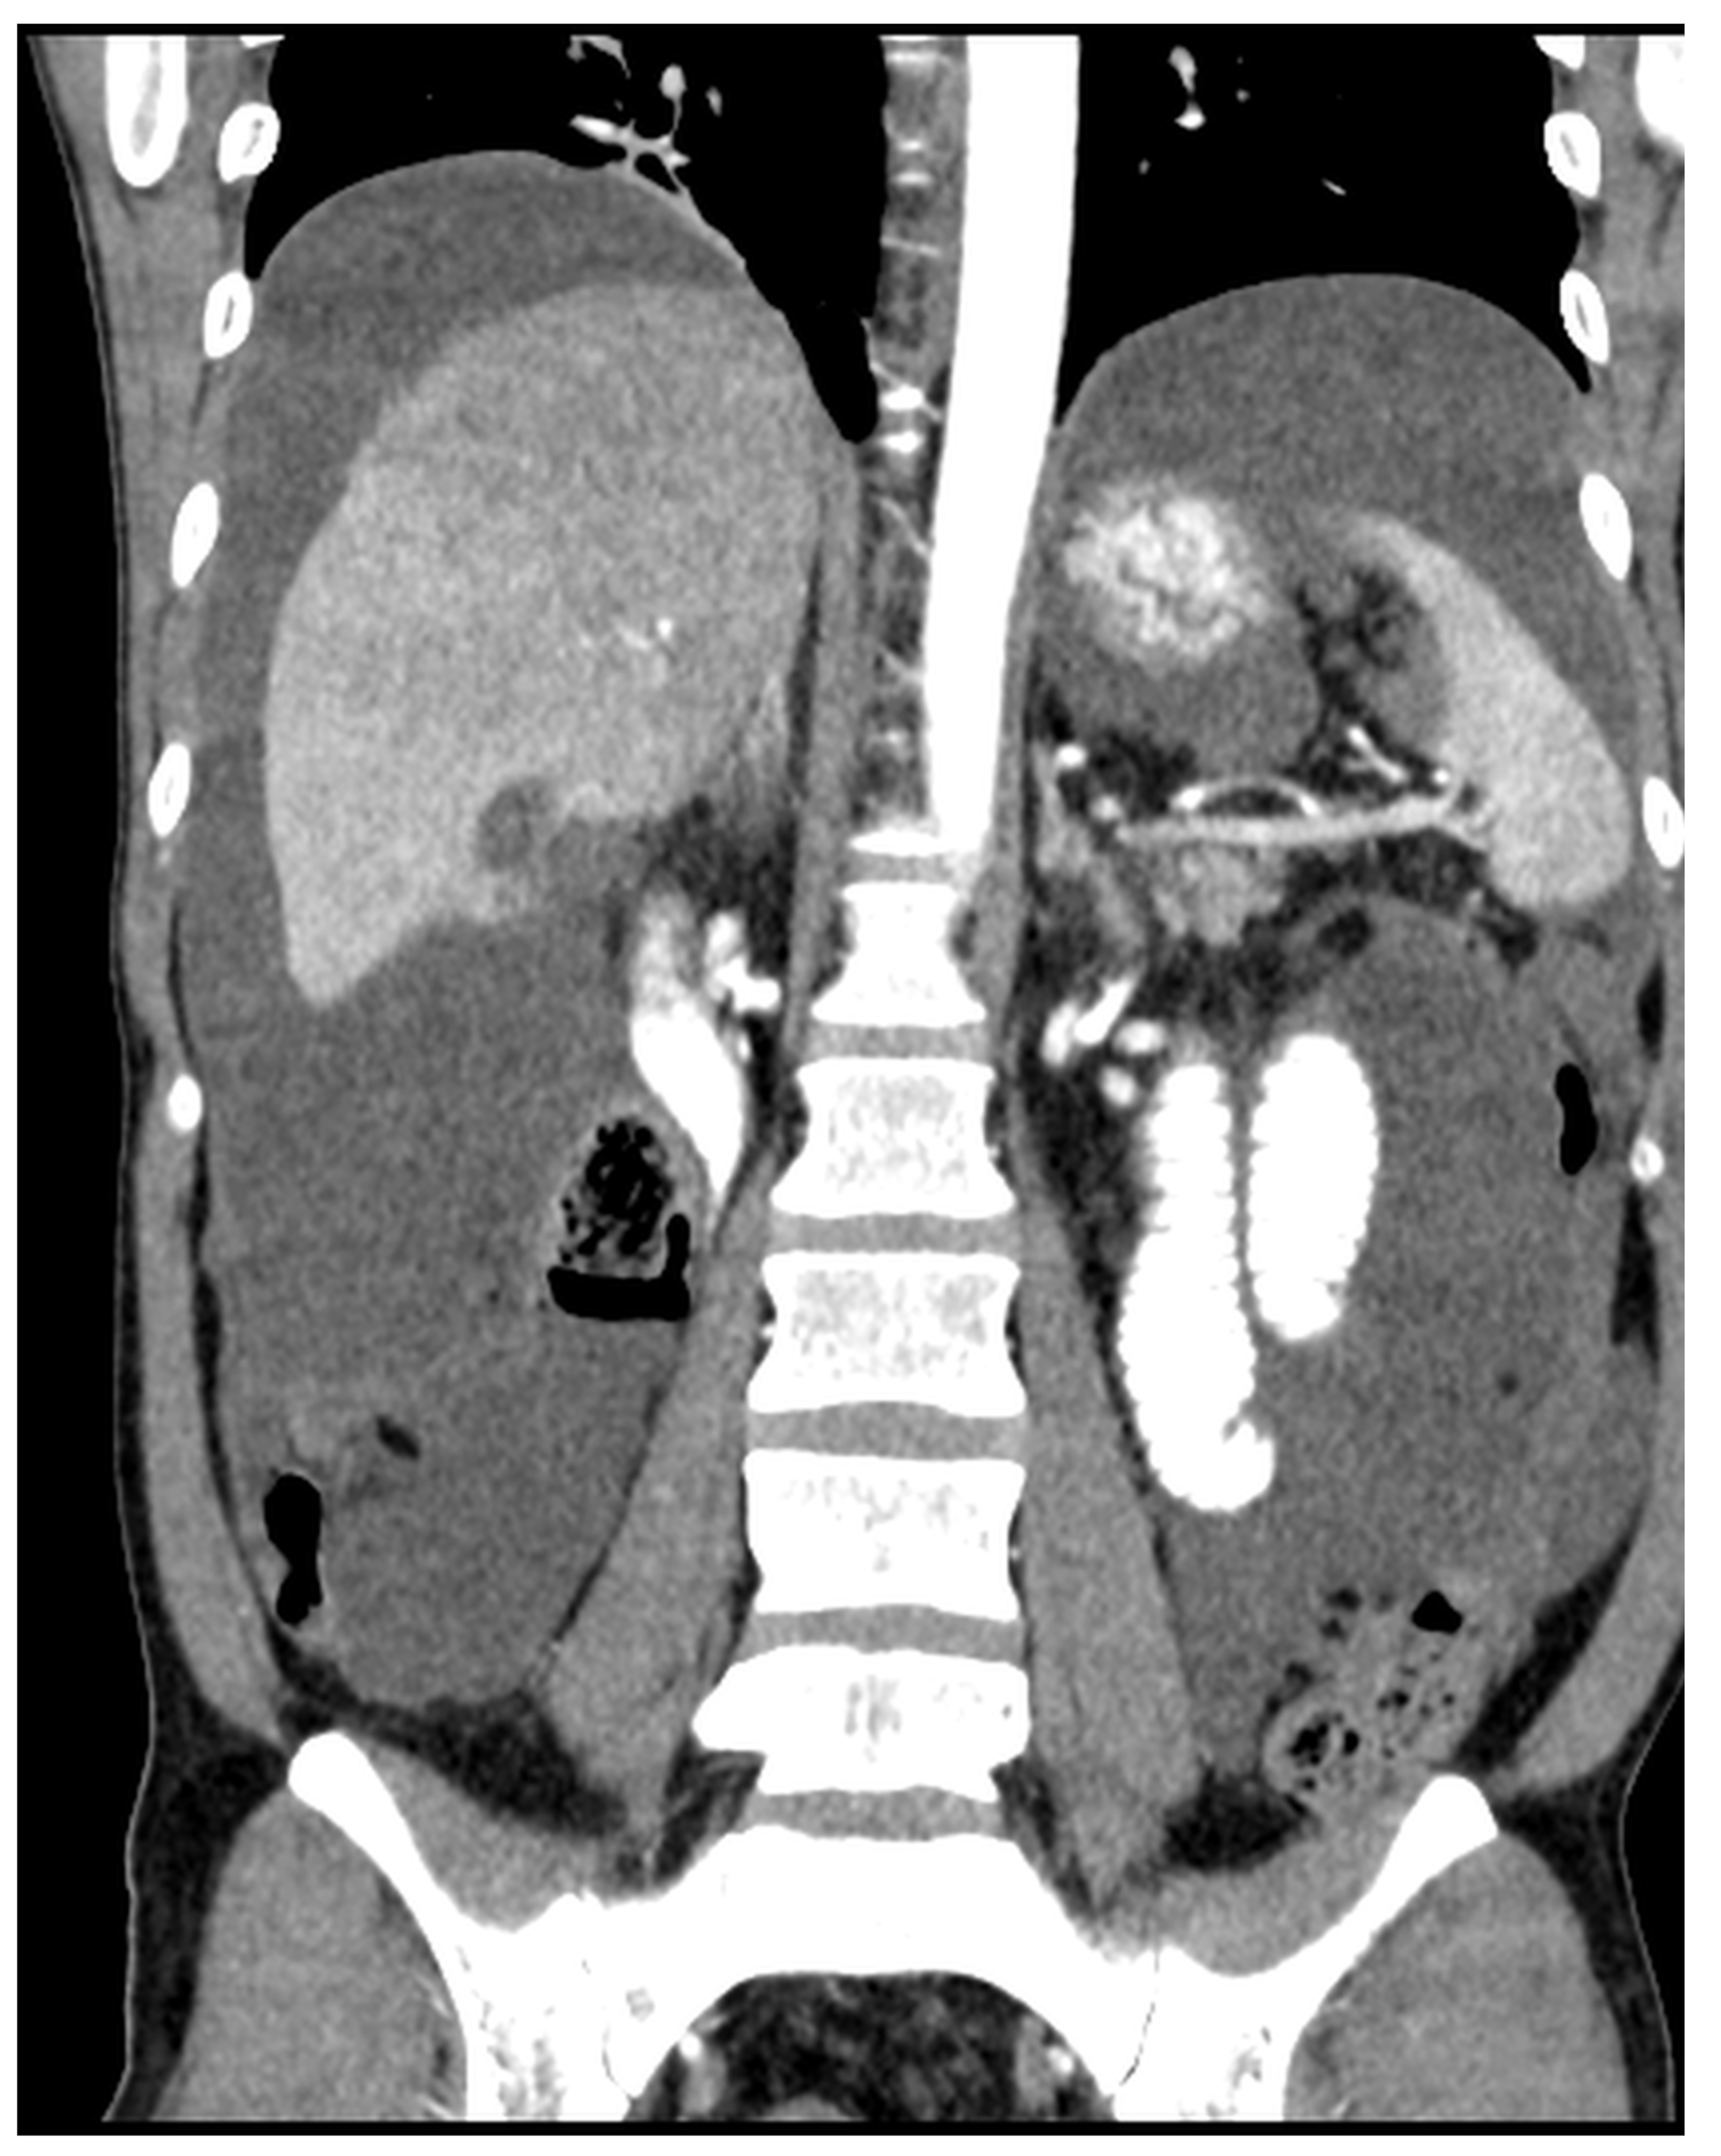

Figure 12. CT, venous phase, coronar plane.

Figure 11, Figure 12, Figure 13, Figure 14 and Figure 15. Advanced stage of the disease. The abdomen is full of tumors and mucin. Typical signs are heterogeneous or hypodense masses in the form of lobules often with septa, which could be enhanced by contrast and could be associated with calcifications.

Patients with a misdiagnosed rupture of the mucocele may develop pseudomyxoma peritonei. It is characterized by the presence of an abundant gelatinous substance in the abdomen. Diffuse, progressive, and abundant mucin-containing tumor cells are typical of this disease [2] (Figure 11, Figure 12, Figure 13, Figure 14, Figure 15 and Figure 16). The interval between rupture and advanced disease is several years. In our clinical series, the interval was about 5 years. In the literature, we found a wide range of this interval from 12 months to 10 years [9,10]. The natural history of PMP revolves around the “redistribution phenomenon”, whereby mucinous tumor cells accumulate in the Douglas pouch, in the diaphragm (more on the right), and the small and large omentum (Figure 17). The small intestine is less involved [4]. Pseudomyxoma peritonei is a slowly progressing disease, which fills the peritoneal cavity over time. There are several classifications of pseudomyxoma. The most commonly used is the PSOGI classification [2]. Mucinous accumulation progresses to malnutrition, bowel obstruction, and respiratory compromise. Rarely, the tumor may spread to the pleural cavity. This has been described in 5.4% of cases. It may occur spontaneously or as a result of diaphragmatic injury during cytoreduction [8,11].